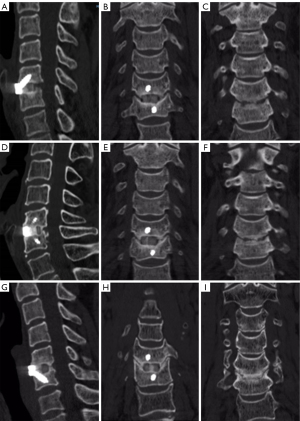

Radiological outcomes: disc height, segmental stability, and subsidence

Both groups showed significant improvements in mean disc height and segmental height postoperatively (P<0.05), with no significant differences between groups at any time point (P>0.05; Table S3). The subsidence rate was similar in both groups (autograft group: 38.8%; allograft group: 36.5%; P>0.05). No cases required reoperation, and no new radiographic foraminal stenosis was detected during follow-up. In addition, we observed a progressive increase in the fusion scores in both groups. At 3 months, the autograft group had higher fusion scores (2.90±0.31) than did the allograft group (2.67±0.52; P<0.05); at 6 months, this trend continued (3.71±0.57 vs. 3.18±0.41; P<0.05); and at 12 and 24 months, fusion scores were similar in both groups (P>0.05; Table S4). Representative postoperative CT images illustrating these differences are shown in Figures 3,4.